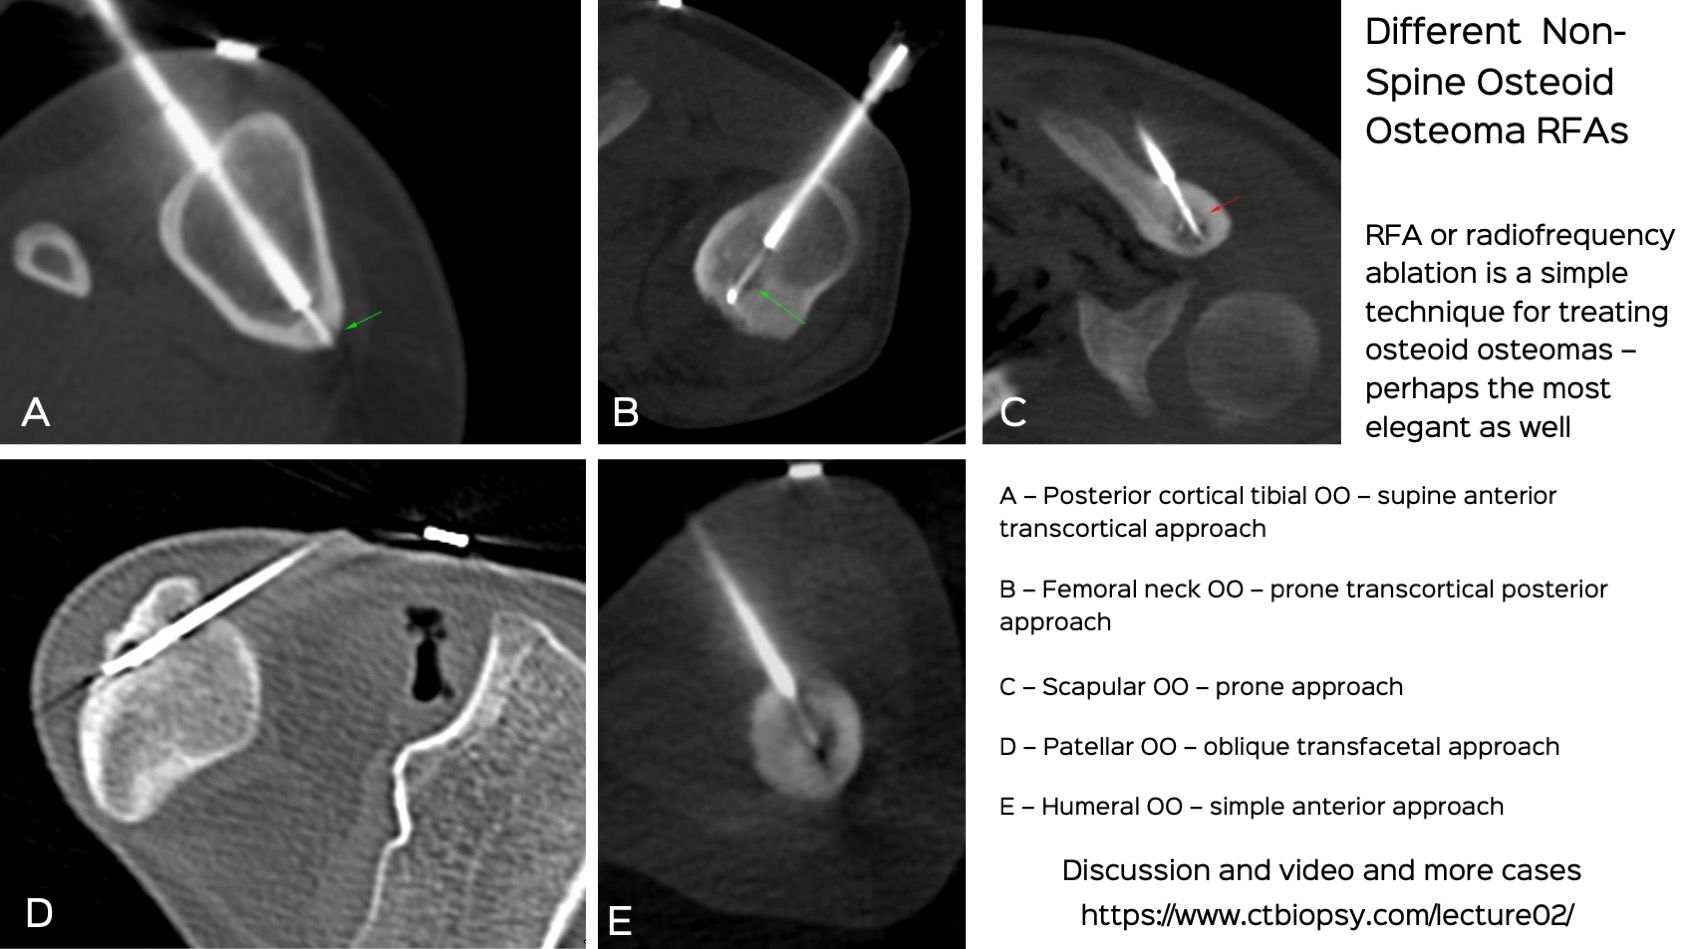

Lecture: Osteoid Osteomas - Treatment Methods Focussing on Radiofrequency Ablation (RFAs)